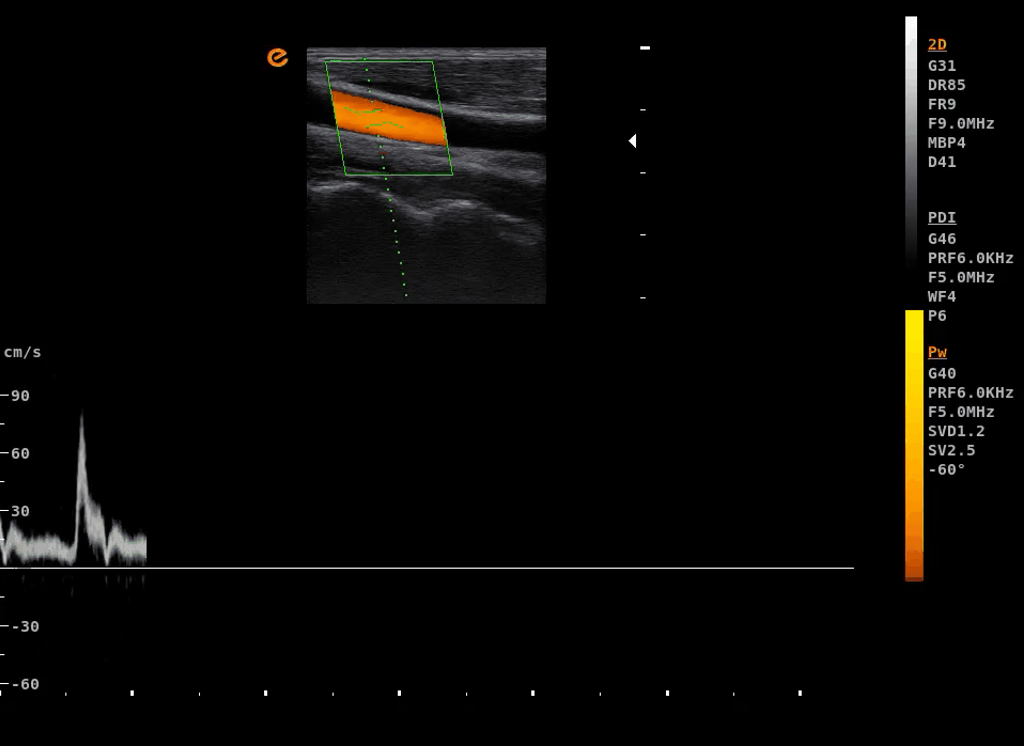

การสกรีนแบบไดนามิกแบบเรียลไทม์สามโหมดพร้อมกัน รองรับการตรวจแบบไดนามิกพร้อมกันใน 3 โหมด ได้แก่ B-Mode, Power Doppler Imaging (PDI), และ Pulsed Wave Doppler (PW) เพื่อการวินิจฉัยที่ครอบคลุมและแม่นยำในเวลาเดียวกัน |